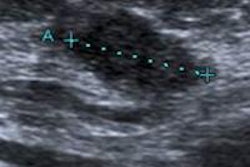

Most breast cancers detected at screening ultrasound are not seen on mammograms, even in retrospect, which suggests that supplemental screening with ultrasound is beneficial for high-risk women -- especially those with dense tissue, according to a new study published in the February issue of Radiology.

In women with dense breast tissue, supplemental screening with ultrasound can find cancers that mammography misses, or those that are too subtle for mammography to identify alone, Bae and colleagues concluded.

"Our data support the idea that screening ultrasound can improve cancer detection in women with dense breasts who are at increased or normal risk," they wrote.